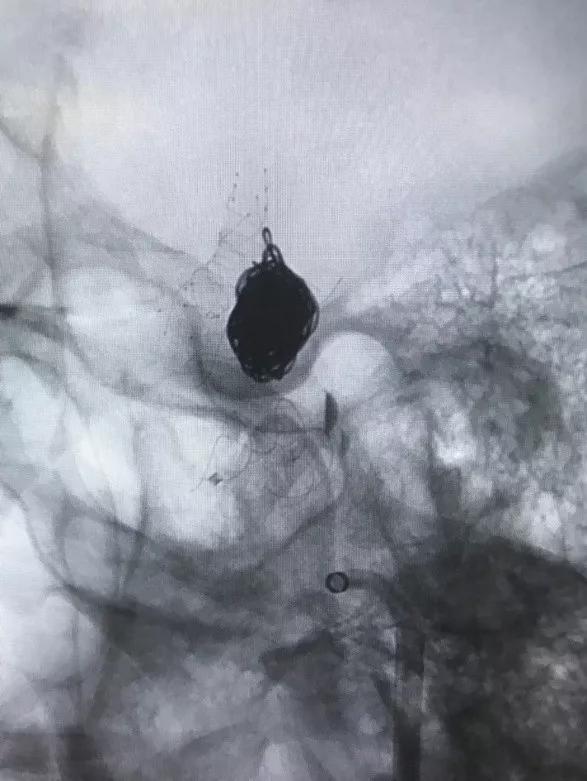

然后再次通过支架并达到右侧大脑中动脉,向海绵窦段多发动脉瘤输送并释放4.0×30mm Tubridge®支架。

▲各角度观察显示Tubridge®贴壁良好

▲造影见造影剂滞留,载瘤动脉通畅。